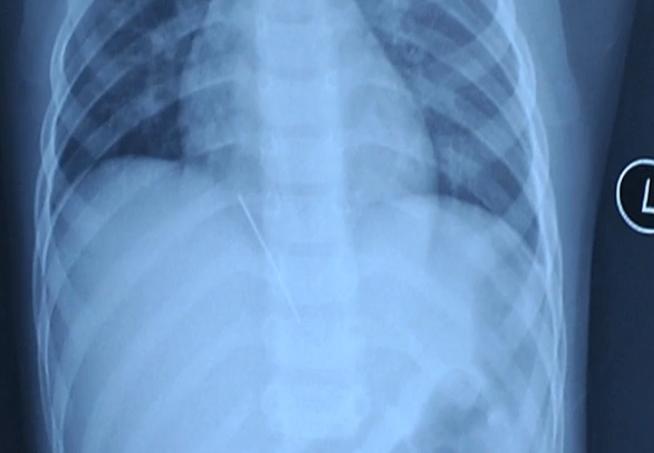

拍片发现,孩子肝脏里面有个金属异物,外表就是根针,从片子上看,大概有四公分!

这可不得了,这根针有可能继续游走,如果走到大动脉,心脏边上刺破血管,将会大出血,引起生命危险!

医生决定立即手术取针,这根针的位置,在肝脏距离心脏的位置非常近,手术难度不小。